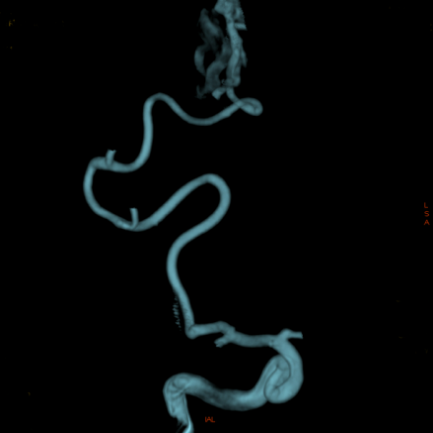

治疗方案及结果: 为了进一步详细观察畸形团形态和大小,需要行3D采集,仅需5秒即可完成血管的三维扫描。  GE提供快速血管提取功能,只需确认血管起点与终点,便可迅速找出供血血管路径,另外,通过使用三维智能路径图可以实时引导治疗过程,

病例点评及临床价值: 由于动静脉畸形团体积较大,且分支血管杂乱无章,因此很难一眼看出畸形团的供血动脉。GE提供快速血管提取功能,只需确认血管起点与终点,便可迅速找出供血血管路径,另外,通过使用三维智能路径图可以实时引导治疗过程,并且在此过程中不论机架、导管床如何变换角度和位置,只要患者相对导管床的位置不变,那么三维智能路径图会始终和患者实际情况完全精准对位,避免了二维路图时需要反复造影的不便。不仅可提高手术精度,还能减少造影剂的使用,节省介入操作时间。